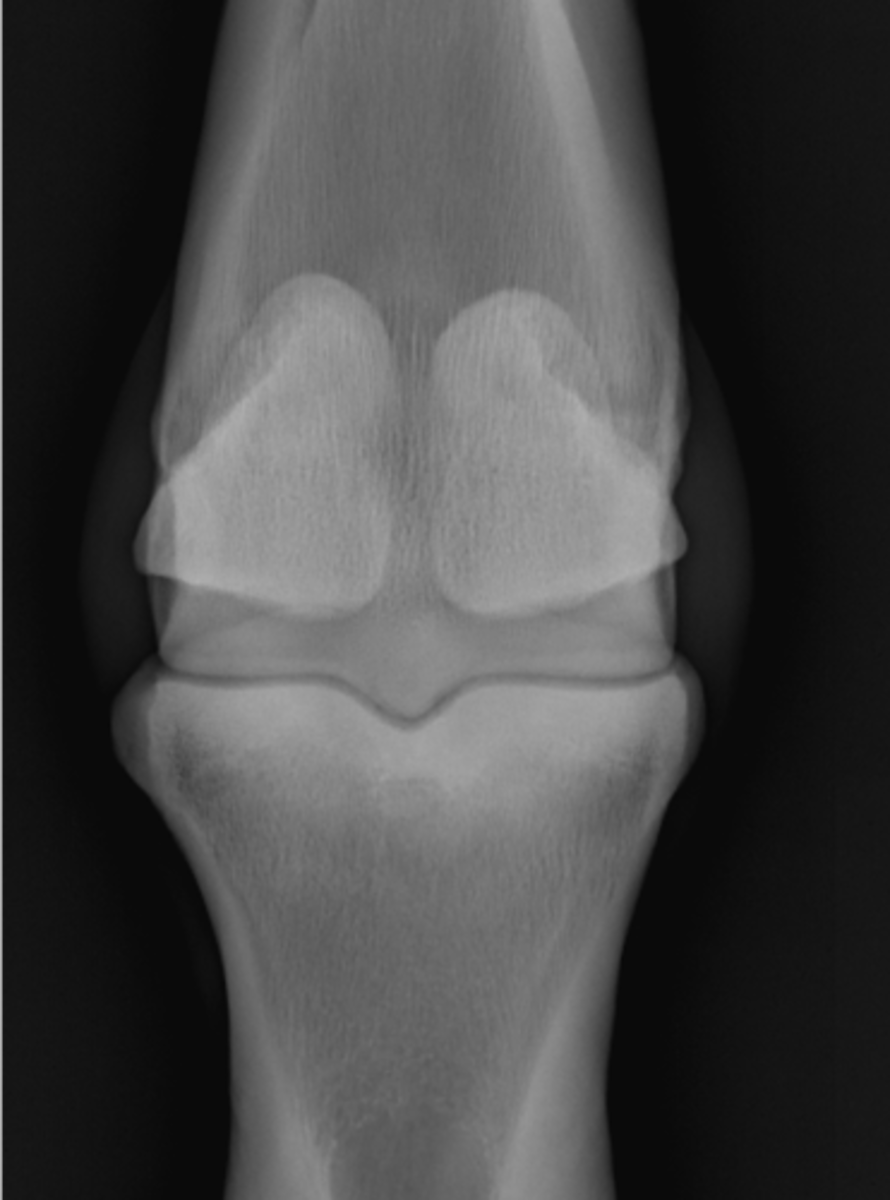

Fetlock joint, DP

ID joint and view